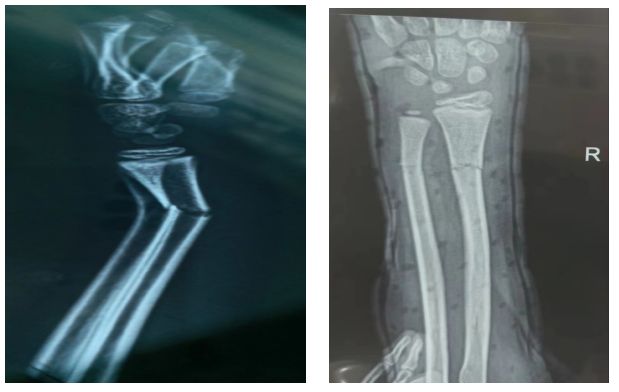

今年八月的一天晚上,叮鈴鈴,我的電話鈴響起,是我家小侄女在玩耍中不小心右臂錯(cuò)位,在當(dāng)?shù)蒯t(yī)院拍片后,醫(yī)生告訴家屬要去上一級(jí)醫(yī)院就診,如果當(dāng)?shù)蒯t(yī)術(shù)高超,孩子不用手術(shù)可以復(fù)位,否則需要鋼板植入。家人抱著忐忑的心情來(lái)到急診外科,正好是王鑫主任值班,他沉著冷靜三下五除二就搞定了,拍片對(duì)照復(fù)位成功,家屬懷著激動(dòng)的心情萬(wàn)分感激。